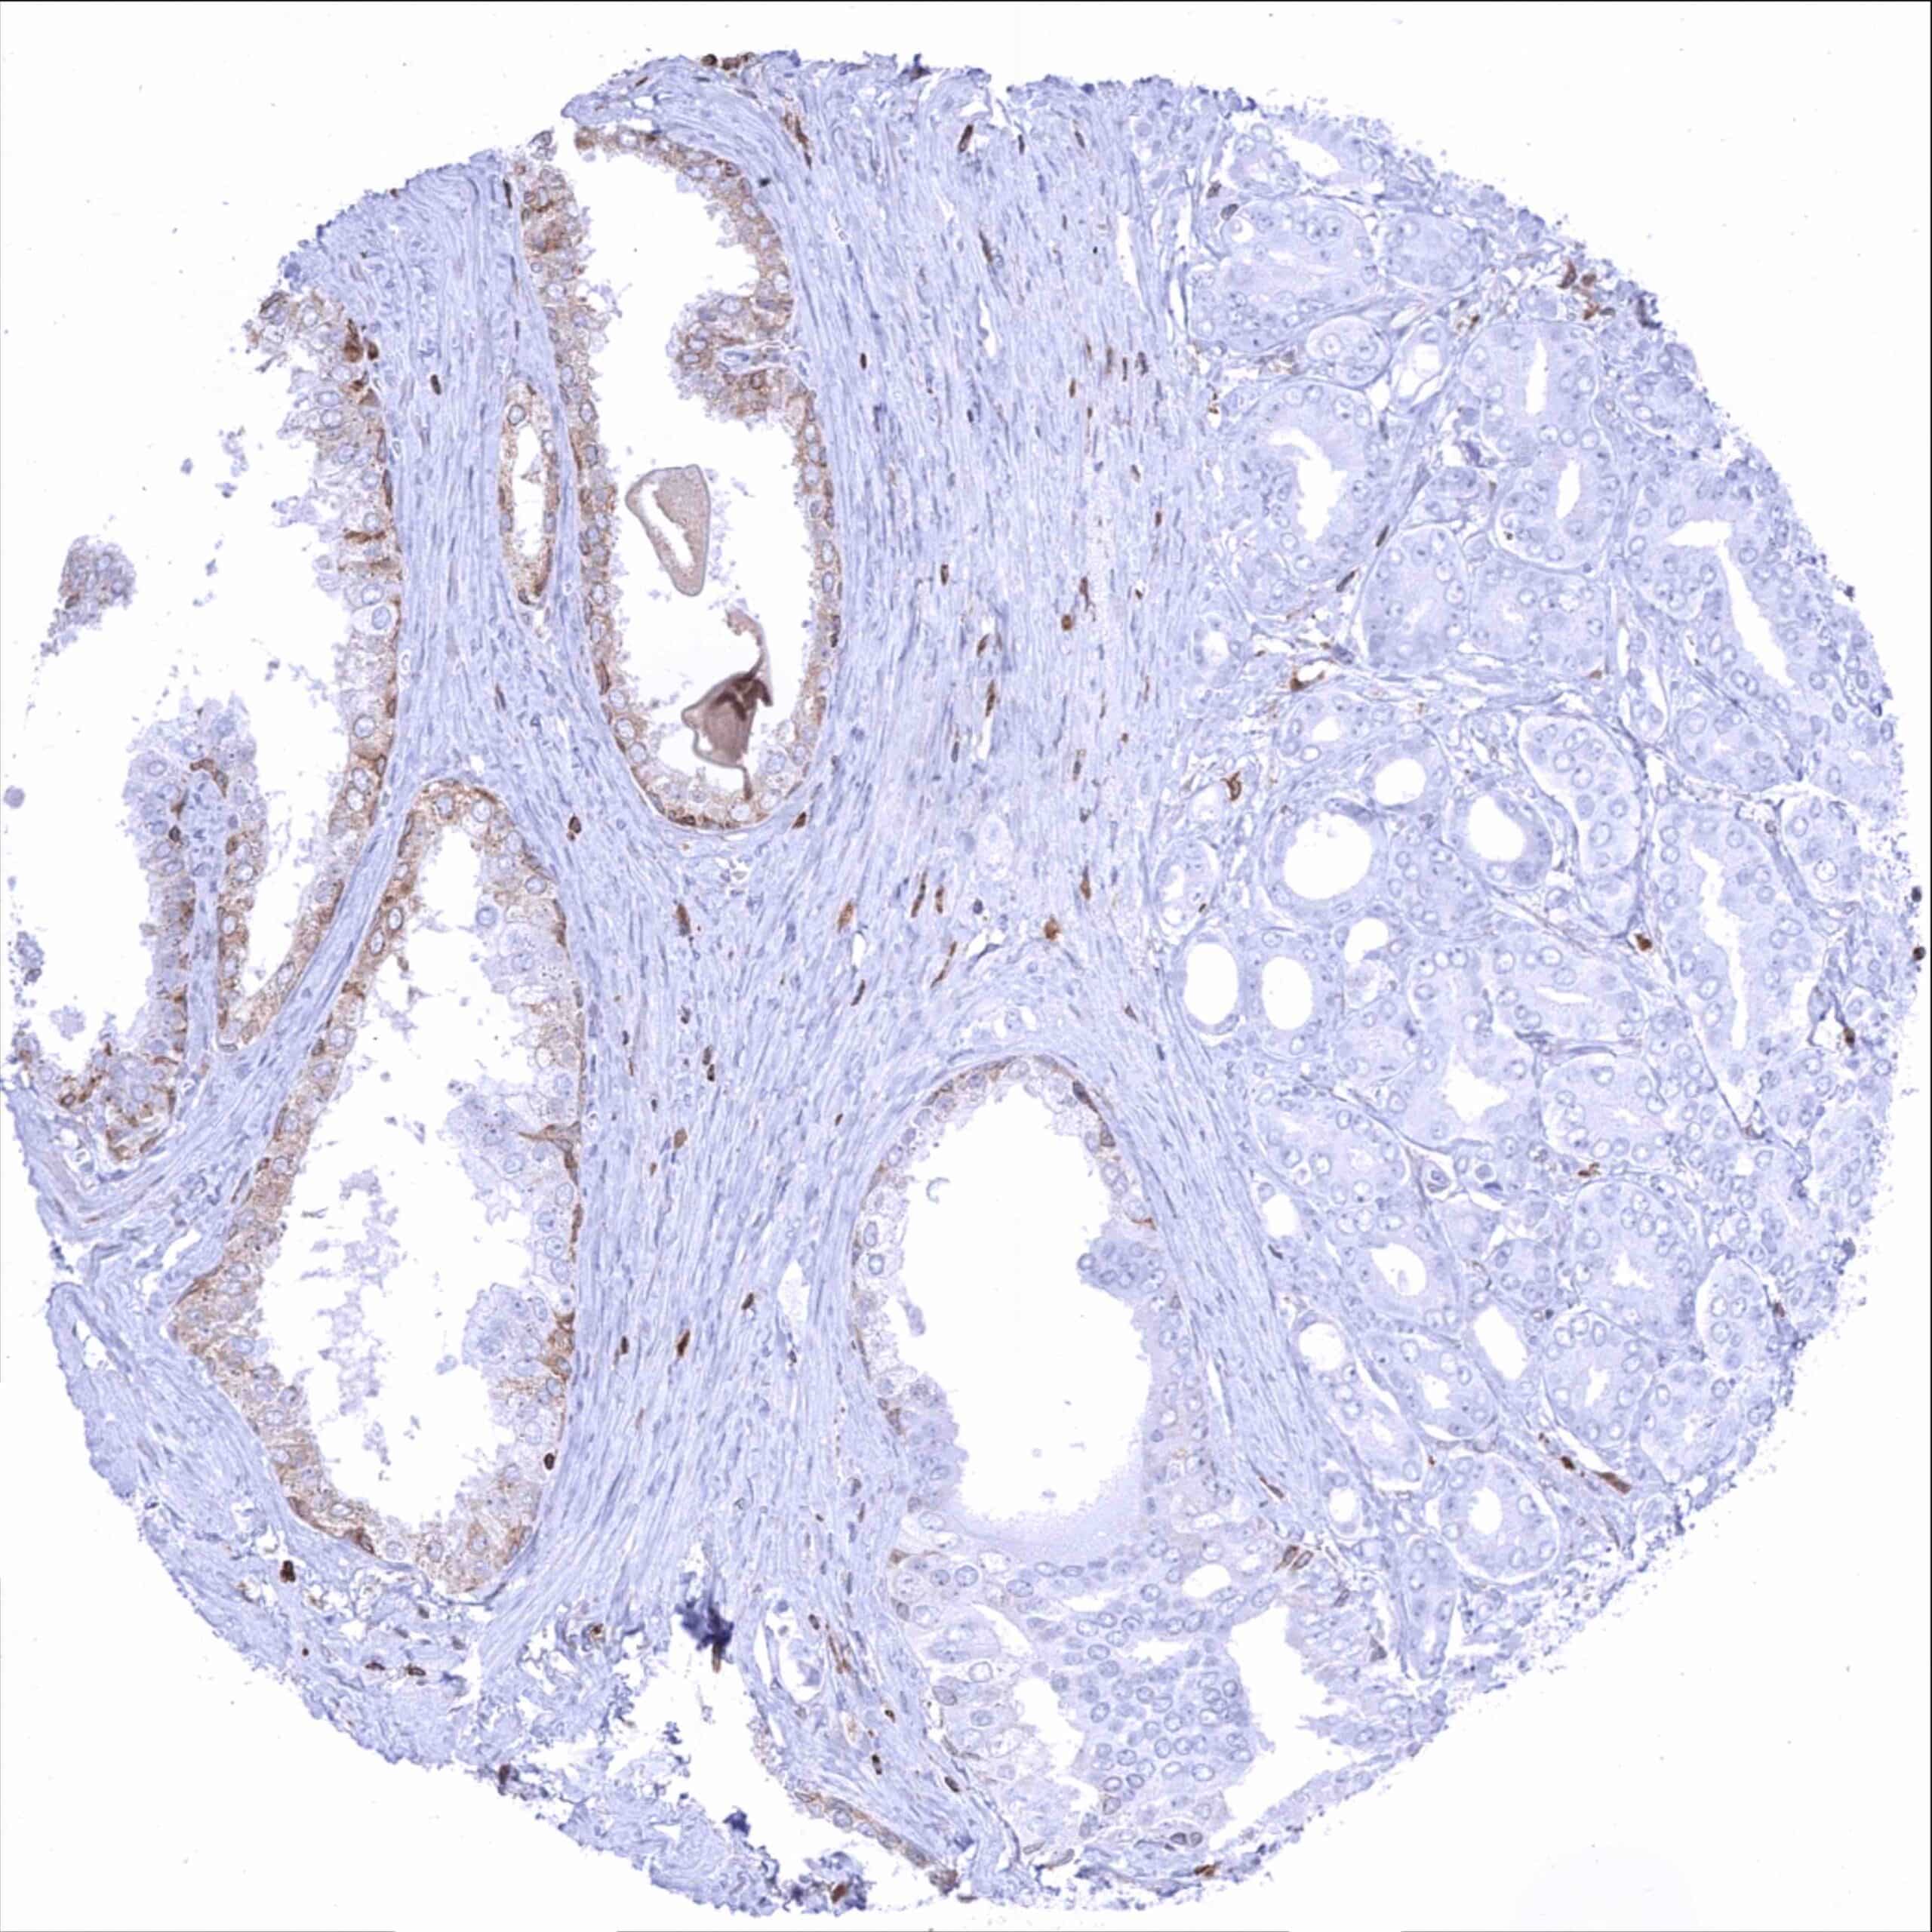

| Lymph node | Strong bcl-2 positivity of a large fraction of lymphocytic cells in the interfollicular area and around germinal centres while almost all cells in germinal centres are bcl-2 negative. | |

| Tonsil | Strong bcl-2 positivity of a large fraction of lymphocytic cells in the interfollicular area and around germinal centres while almost all cells in germinal centres are bcl-2 negative. Squamous epithelium is bcl-2 negative although the basal cell layer may show weak positivity. | |